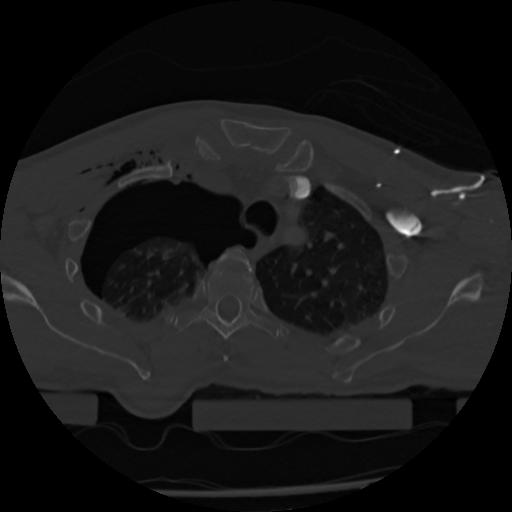

22 ANGIO,CE,Vol,0.5,ANGIO,,